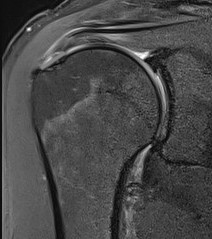

Bursal Sided